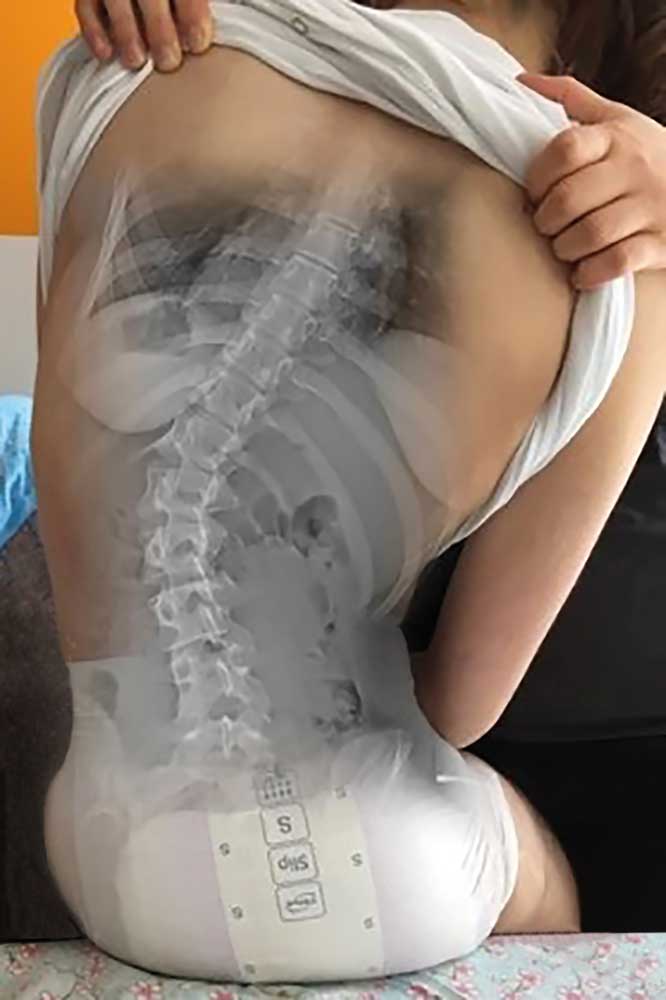

Standardisierte anterior-posteriore (a.-p.) Röntgenbilder wurden retrospektiv ausgewertet. Die Aufnahmen wurden bei allen Patienten in sitzender Position durchgeführt. Bei 3 Patienten wurden Röntgenbilder in stehender Position angefertigt. In liegender Position angefertigte Röntgenbilder waren nicht zulässig, da das maximale Ausmaß der Verkrümmung in dieser Position durch die fehlende Schwerkraft nicht sichtbar ist. Anhand der a.-p. Röntgenbilder wurden der Apex sowie die lumbalen und thorakalen Cobb-Winkel berechnet. Alle Winkel wurden mittels „Centricity Dicom Viewer V3.1“ gemessen. Bei demselben Krankenhaustermin wurden zwei Röntgenbilder angefertigt: eine erste Röntgenaufnahme (T1) mit Doppelschalenkorsett und nach 5 Minuten (T0) ein zweites Röntgenbild ohne Korsett. Dies war allerdings nur bei Patienten mit korrekter Anpassung des Doppelschalenkorsetts möglich. Bei den anderen Patienten betrug die Zeitspanne zwischen T1 und T0 nicht mehr als 3 Monate aufgrund notwendiger Anpassungen des Doppelschalenkorsetts durch den Orthopädietechniker. Der Grad der Korrektur des Cobb-Winkels im Bereich der Lenden- und Brustwirbelsäule wurde in Prozent des Messergebnisses ohne Korsett bei T0 ausgedrückt (Abb. 1 u. 2).

In allen Fällen wurde, wie von Rutz et al. im Jahr 2013 39 beschrieben, ein Doppelschalenkorsett verwendet. Es handelt sich um ein maßgefertigtes Korsett (Abb. 1), das einfach zu handhaben ist. Das Doppelschalenkorsett besteht aus einer vorderen (ventralen) und einer hinteren (posterioren) Schale. Diese beiden Teile sind je ca. 6 mm dick. In der Regel funktioniert das Korsett mittels Druckpelottensystem, wobei eine gute Beckenfassung essentiell ist. Darüber wird zunächst die hintere Schale aus 5 mm starkem PE tiefgezogen. Diese sollte den Rumpf zu ca. 60 % umschließen und wird nach vorne ausgedünnt. Darüber wird eine vordere Schale gezogen, die großzügig gefenstert wird, um Nahrungsaufnahme und Verdauung nicht zu beeinflussen. Der vordere Rahmen dient vornehmlich dazu, den Körper in der hinteren Schale zu fixieren. Damit die Position zwischen vorderer und hinterer Schale sicher reproduziert werden kann, werden an der hinteren Schale Führungsbolzen angebracht und in der vorderen Schale Führungsschlitze vorgesehen. Eltern bzw. Pflegern wurde empfohlen, das Doppelschalenkorsett über einen Zeitraum von 6 bis 8 Stunden pro Tag am betroffenen Patienten in Positionen anzuwenden, in denen die Schwerkraft Einfluss auf die Wirbelsäulenverkrümmungen nehmen kann, also z. B. in sitzender oder stehender Position, aber nicht während des Schlafes oder im Liegen.

Die Abbildungen 3 und 4 zeigen die klinischen und radiologischen Befunde für eine 18-jährige Frau (Fall 17). In Abbildung 3 sind die klinischen Fotos ohne und mit Doppelschalenkorsett zu sehen. Abbildung 4 zeigt die Röntgenbilder dieser Patientin ohne (a) und mit (b) Doppelschalenkorsett.